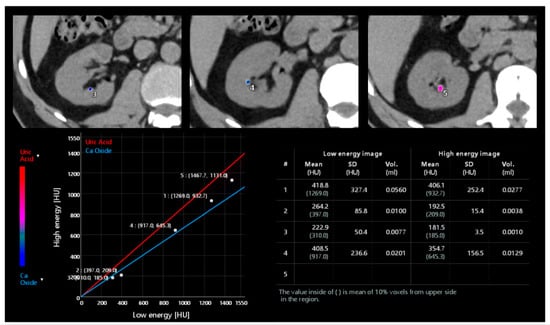

DECT demonstrated high accuracy in the distinction between uric acid calculi from non–uric acid calculi [68,69] and provided information for evaluating stone fragility (Figure 9) [70].

Figure 9.

Post-processing analysis of a dual-energy unenhanced kidney acquisition. Different stones can be analyzed to characterize their composition as uric acid, calcium oxide, or mixed composition according to the position of the point related to the straight lines of the two materials. Moreover, an automated calculation of volume and mean Hounsfield Unit is available.

According to attenuation levels, the composition of the stones can also be classified as hydroxyapatite, uric acid, cysteine, oxalic acid, and mixed stones [71]. Accuracy in stone characterization decreases when evaluating calculi < 3–5 mm due to the difficulty in obtaining accurate attenuation values [72].